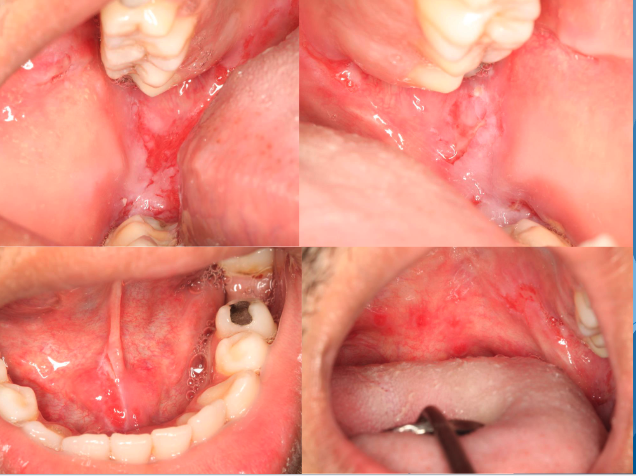

Desquamative Gingivitis

Desquamative Gingivitis have a predilection for what gender?

females

Desquamative Gingivitis may display sensitivity to…?

spicy foods

what condition?

• Diffuse, markedly erythematous gingiva

• Generally involves attached tissues